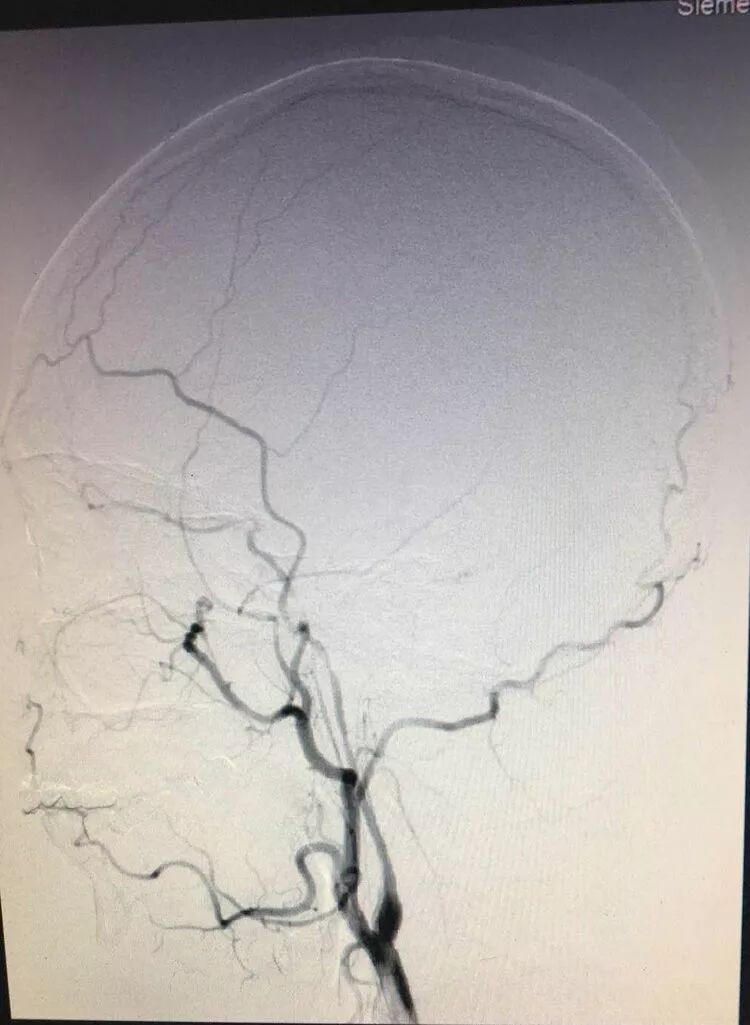

27岁的小萍,本是最好的年华,可以享受生活、岁月和阳光。然而可能上帝就是不能给一个人完美,2017年11月小萍在毫无征兆的情况下频繁出现左侧肢体活动不灵,在1个月后突发左半身肢体无法活动。MR提示右侧枕叶新发梗塞,头DSA提示右侧大脑中动脉闭塞,诊断烟雾病。临床分期及分型:Suzuki及Takaku III期,Matsushima III型。

术后3个月,全脑血管造影复查见血管吻合确切,血流通畅,另外造影显示颞肌也对颅内形成了代偿供血。